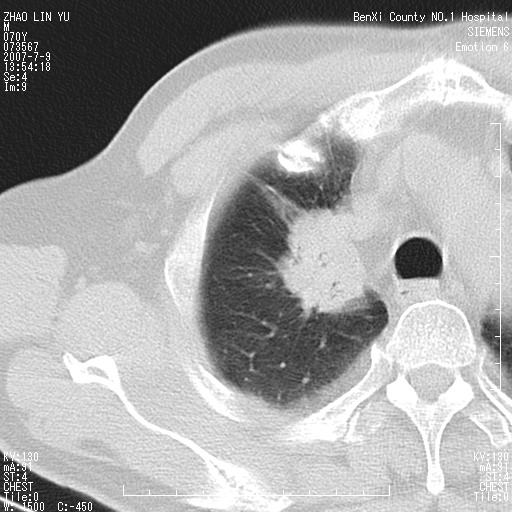

以下是引用王靖旗在2007-7-10 17:12:00的发言:[br] 男、70、咳嗽两个月,半年前换瓣手术,胸片未见异常,于昨天行x片发现右肺上野大片影,行ct扫描,这里是减薄图像,余肺正常。明天晚上会有增强扫描片,到时我会上传。[br][br] 冠状位请大家细看,应该是有意义的,[br][br] 请大家先看平扫发表意见。[br][br]

以下是引用zhangzhongshou在2007-7-10 21:43:00的发言:[br]右肺上叶周围型肺癌,以孤立型细支气管肺泡癌可能性大。